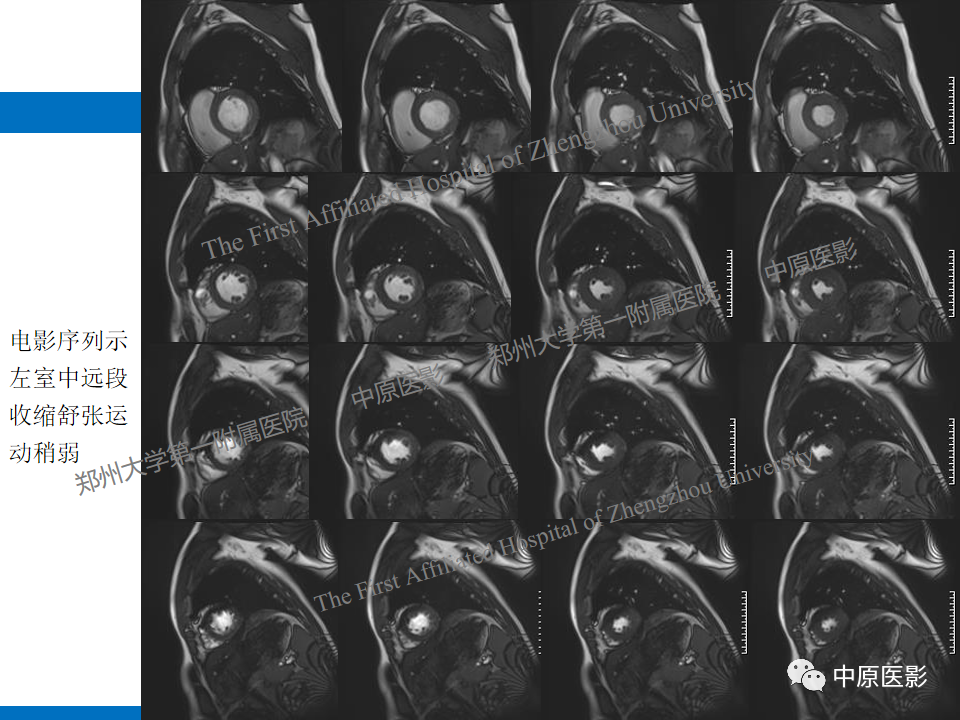

【病例】致心律失常性右室心肌病1例MR影像-1